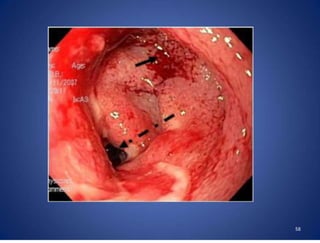

Endoscopy □ Colonoscopy isof value to rule out malignancy. □ It is easiest and most direct method in establishing the diagnosis. □ Shows mucosal nodules or ulcers , deformed ileo caecal valve, mucosal oedema and pseudopolyps and occasionally diffuse colitis. Biopsy can be taken to confirm diagnosis. □ Capsule endoscopy is also useful to see small intestine pathology in difficult cases . 56

□ Nodules □ Variablesizes (2 to 6mm) □ Non friable □ Most common in caecum especially near IC valve. □ Tubercular ulcers □ Large (10 to 20mm) or small (3 to 5mm) □ Located between the nodules □ Single or multiple □ Transversely oriented / circumferential contrast to Crohns □ Healing of these ‘girdle ulcers’^ strictures □ Deformed and edematous ileocaecal valve 57